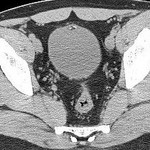

[画像診断]バルトリン腺嚢胞について(Bartholin gland cysts) 2010-10-12